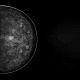

PH-83 可変型乳房ファントム Comp-AY型

3Dマンモグラフィにも対応した可変する乳房ファントム

●特殊な軟質素材で作られており、実機を用いて実際に圧迫しながら撮影することができます。

●2Dマンモグラフィ撮影はもちろん、3Dマンモグラフィ撮影も行えます。

●大きさやX線透過率の異なる腫瘤/模擬乳腺/石灰化がそれぞれ複数個含まれています。

●ファントム本体を回転させることで、内容物の位置を変えて撮影することも可能です。